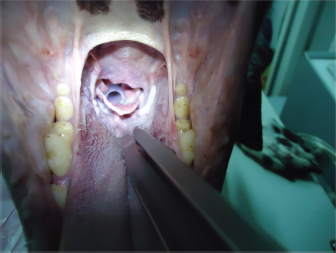

In dogs that showed an elongated soft palate, first palatoplasty was performed under general anesthesia and second placement of the silicone stent was performed as described above (Fig. 5), with the exception of the Brittany Spaniel where stent placement was only therapeutic due to costs of the palatoplasty surgery (Fig. 4). Two dogs (dog’s number 6 and 7) had prior to the laryngeal stent placement, a ventriculocordectomy through ventral laryngotomy, castellated laryngofissure, and palatoplasty because of laryngeal paralysis and elongated soft palate. The days after, the surgery normal respiratory sound was perceived, but the female Labrador Retriever coughed during water swallowing. Seven to ten days after the surgery, stridor relapsed in both the dogs. Laryngeal stenosis was confirmed in the glottis due to fibrosis reaction to the cordectomy. Thus, the laryngeal stent was placed for the treatment of the stenosis pathology and laryngeal paralysis. All dogs presented normal breathing sounds after the laryngeal stent placement. Case 1 was diagnosed with general megaesophagus and bronchopneumonia, regurgitation was constant, and euthanasia was performed for humanitarian reasons. The owners of dog’s number 1 and 2 decided the euthanasia several days after the laryngeal treatment for economic reasons of the diagnostic etiology and progressive weakness. In both the dogs, the stent was retrieved from the larynx, and mild inflammatory reaction was observed. Diagnosis, treatment, and survival time for each clinical case are summarized in Table 2.

Fig. 5. Correct position of the stent.